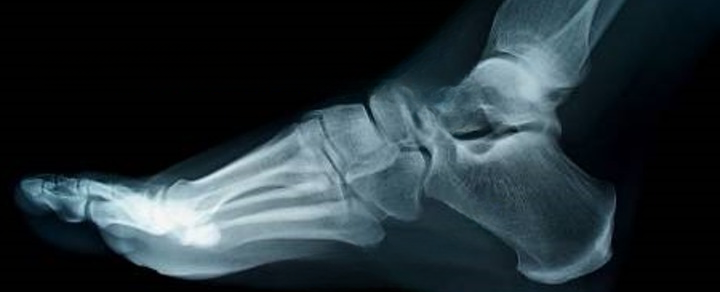

HyProCure corrects irregular foot form and alignment. The procedure uses an incision in your arch to correct the misaligned bones in your foot, allowing your bones to move freely again. HyProCure also reduces pressure on nerves, which can cause pain and inflammation.

HyProCure is place in the naturally occurring space between your bones to instantly realign and stabilize the hindfoot. It will not penetrate or be implanted into your bones.